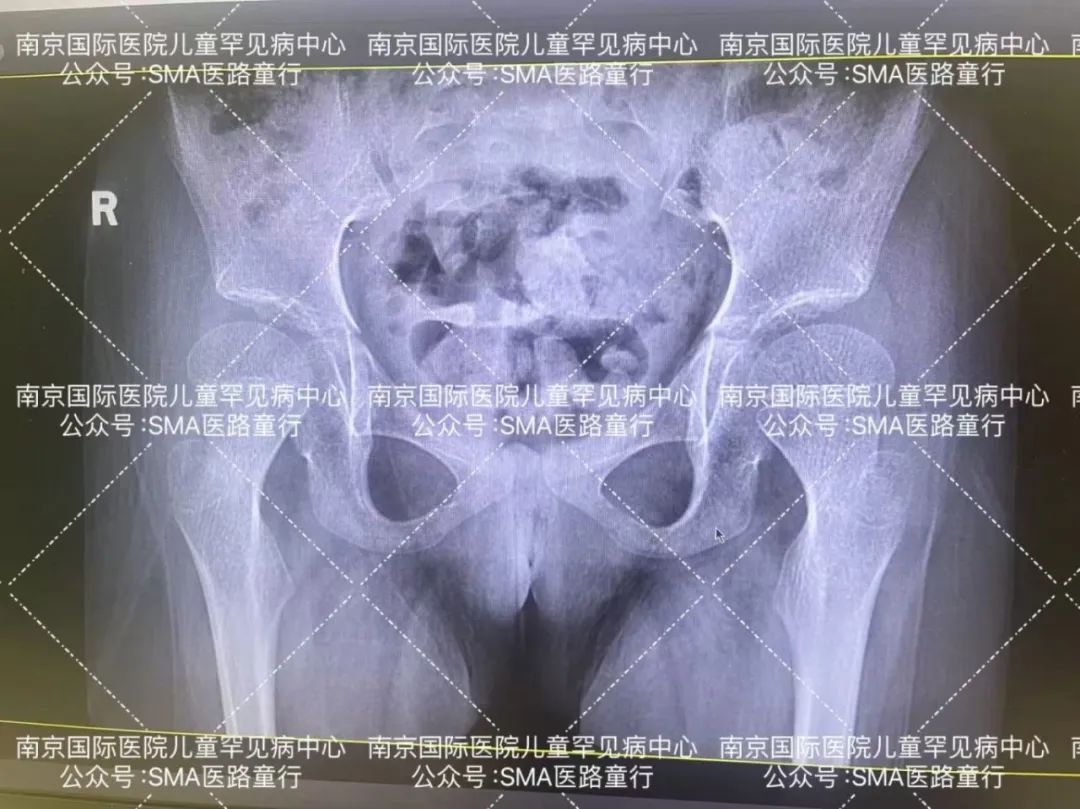

*入院前的骨膜摄影